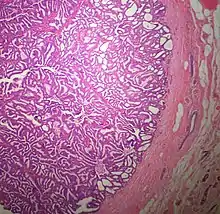

The microscopic histopathology of typical PDCIS lesions (refer to adjacent high-power photomicrograph) prepared with a hematoxylin and eosin stain consists of mammary ducts that have papillary fronds (i.e. thin, finger-like or leaf-like structures) lined with one or several layers of neoplastic, columnar-shaped epithelial cells (i.e. tall, narrow cells with their nuclei close to the site of their ductal attachment).[4] The fronds have branching fibrovascular cores. Epithelial cells lining the fronds' inner surfaces commonly form solid, cribriform (i.e. large nests of cells perforated by many rounded, variably sized spaces), or micro-papillary patterns. There may be a second population of epithelial cells lining the papillae that have abundant clear cytoplasm in addition to the usual neoplastic epithelial cells which line the papillae. These cells, which are not myoepithelial cells, have been termed globoid cells.[7] They have eosinophilic cytoplasm (i.e. pink or red cytoplasm due to its uptake of eosin stain).[6] PDCIS tumors with these cells have been termed dimorphic variants of PDCIS.[3] Myoepithelial cells are typically present at the periphery of the fronds but absent within the involved ducts.[4][7] The presence of a fibrous capsule and/or absence of peripherally located myoepithelial cells are strong indicators that the tumor is an ESP rather than a PDCIS.[3] PDCIS tissues may also contain areas of "Comedo-type necrosis", i.e. areas where dead cells have accumulated.[6]

Microscopic histopathological analyses of SPC lesions (refer to adjacent high-power photomicrograph) generally show tumors with multiple circumscribed nodules of expanded ducts filled with neoplastic epithelial cells which may appear spindle-shaped or plasma cell-like, have red to pink cytoplasm due to the uptake of eosin after staining with hematoxilin & eosin, and eccentrically-placed nuclei. Rarely, signet ring-shaped cells are present. The tumors may have cystic and hemorrhagic areas. Myoepithelial cells are found within and at the periphery of these tumors. The papillary architecture seen in the other SCB types is in general not apparent; rather, pseudo-rosettes (i.e. radial arrangements of neoplastic cells around small blood vessel) and nuclear palisading (i.e. parallel arrangements of the nuclei in rows of tumors that resembles picket fences) around stromal cores (i.e. supporting tissues) may be seen. SPC tumor tissues typically (>50% of cases) have areas of neuroendocrine differentiation. The presence of these areas strongly supports the diagnosis of SPC.[21] The signet ring-shaped cells in these tumors contain cytoplasmic mucin-containing vacuoles which push their cells' nuclei to one side.[10] Mucin may also occur outside of cells in these lesions. The presence of signet ring-shaped cells bearing mucin-containing vacuoles with or without extracellular mucin strongly supports the diagnosis of SPC. SPC is considered invasive when the tumor nests have a characteristic jigsaw growth pattern with ragged and irregular margins with the loss of myoepithelial cells at the site(s) of invasion.[21] Rarely, invasive SPC occurs with nearby invasive carcinoma of NST, lobular carcinoma, cribriform carcinoma, or tubular carcinoma breast tumors.[3]

Since many of the earlier published cases of IPC actually appear to be variants of invasive EPC or SPC, there is little consistent pathological data on IPC.[7] Studies on the microscopic histopathology of IPC have reported finding (refer to the adjacent high-power photomicrograph): 1) blunt papillae or ductal structures consisting of neoplastic epithelial cells surrounding a fibrovascular core;[1] 2) papillae located in dilated ducts and variably sized microcysts plus foci of necrosis (i.e. dead cells);[4] 3) tumors totally dominated by fibrovascular cores covered with neoplastic epithelium cells;[3] and 4) tumors showing >90% papillary morphology invading nearby breast tissue and/or sub-mammary chest muscles.[22] Studies do agree that IPC tumors have, by definition, one or more sites that have invaded nearby breast and/or muscle tissue, lack myoepithelial cells at their invasion sites, and generally lack a peripheral fibrous capsule; these features are important for diagnosing IPC.[6][7][20][22] Rarely, ductal carcinoma in situ lesions are present near IPC.[3] A retrospective histopathological analysis of the tumor tissues in 1,147 individuals with IPC reported that 89.3%, 83.4%, and 2.4% of the cases had tumor cells which respectively expressed the estrogen receptor, progesterone receptor, and HER2/neu protein (however, 46.4% of the cases were not tested for the HER2/neu).[1] In a second histopathological study of 44 individuals diagnosed with IPC, 72.7% had tumor cells that expressed the estrogen receptor, 72.7% had tumor cells that expressed the progesterone receptor, and 13.6% had tumor cells that expressed the HER2/Neu protein.[22] No specific genetic alterations have been as yet been clearly associated with the tumor cells in individuals diagnosed with IPC.[6]